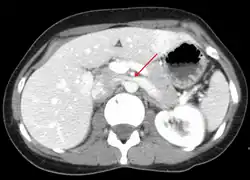

CT and MRI

CT and MRI with contrast can be used afterward to confirm compression by the AA and SMA with comprehensive measurements of the abdominal vasculature. A "beak sign" can often be seen in CT scans due to the LRV compression. However, CT and MRI cannot demonstrate the flow within the compressed vein. These two modalities can be used to confirm other evidence for NCS such as back-up of blood flow into the ovarian veins.[11][6]